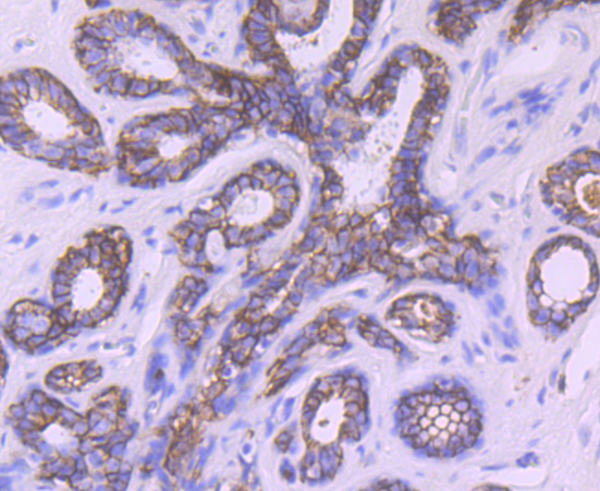

TROP2, Polyclonal Antibody (Cat# AAA29936)

Full Name

TROP2 Antibody

Gene Names

TACSTD2; EGP1; GP50; M1S1; EGP-1; TROP2; GA7331; GA733-1

Reactivity

Human

Applications

Western Blot (WB), Immunocytochemistry (ICC), Immunohistochemistry (IHC)

Purity

Protein affinity purified

Pricing